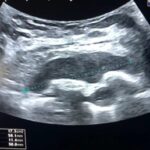

Paciente femenina de 26 años de edad, sin antecedentes patológicos de relevancia, sin dosis de vacuna BCG. Cursa con cuadro clínico de ocho meses de evolución, caracterizado por dolor en región pectoral izquierda intermitente, que se exacerba a la inspiración profunda. En el último mes se palpa masa indurada dolorosa a la palpación a nivel del cuadrante inferior interno de mama izquierda, motivo por el cual se realiza ecografía de partes blandas, donde se observa a nivel retropectoral en íntimo contacto con la parrilla costal imagen hipoecogénica de bordes delimitados, avascular al Doppler color por lo cual se solicita TC de tórax con EV. En ella se observa en topografía del cuarto espacio intercostal, imagen hipodensa con realce periférico tras la administración del contraste que desplaza por efecto de masa el parénquima pulmonar adyacente y se proyecta a la pared torácica anterolateral izquierda; mide 40 mm x 55 mm. Además, se visualiza otra imagen de similares características de base pleural en contacto con el octavo arco costal posterior izquierdo que mide 6 mm x 11 mm.

La ecografía pleural es útil para evaluar la cantidad de líquido y guiar procedimientos como la toracocentesis.